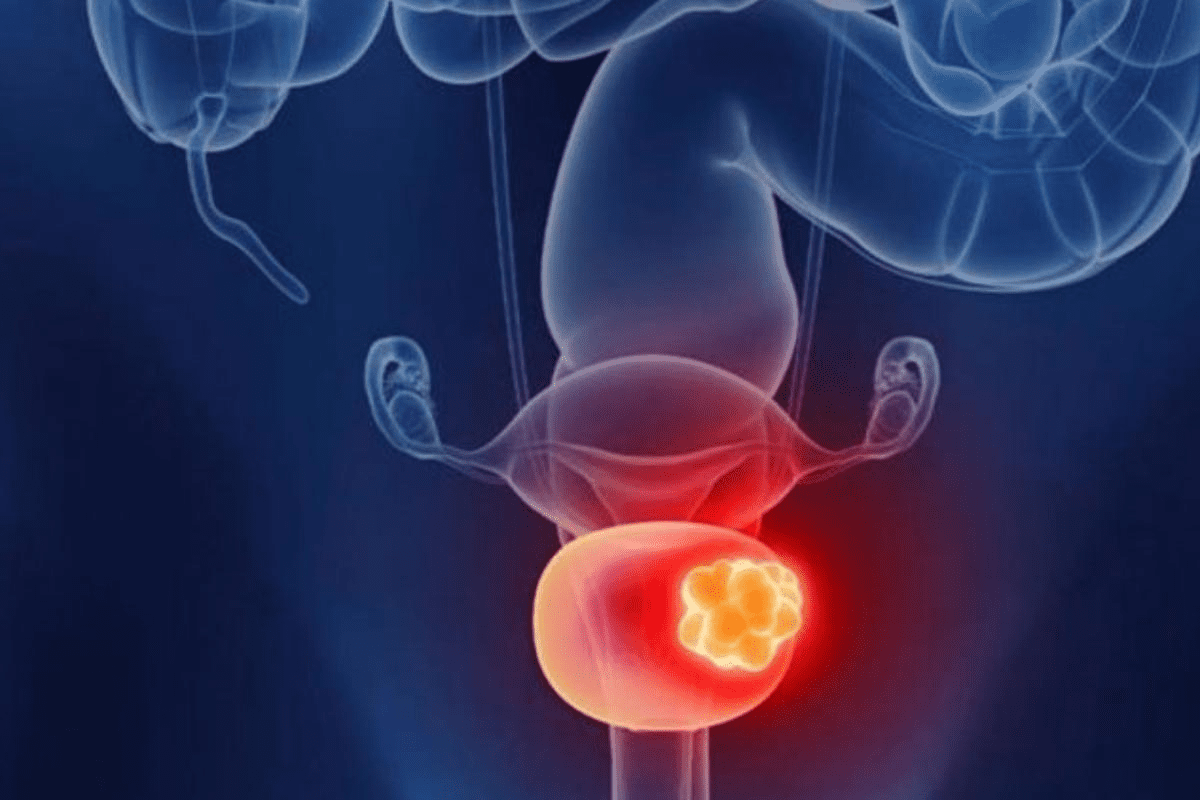

Understanding Solid Tumors: Definition and Classification

It’s key to know about solid tumors to fight this serious disease. Solid tumors are abnormal tissue masses that can be benign or malignant. They grow out of control, causing health problems based on where they are and what they are.

Distinguishing Solid Tumors from Other Cancer Types

Solid tumors are different from liquid tumors like leukemia. Liquid tumors affect the blood and bone marrow. Solid tumors, on the other hand, form masses that can be felt or seen on scans. This difference is important for diagnosis and treatment.

Common Types of Solid Tumors

Solid tumors are grouped by where they start and how they look under a microscope. The main types are:

Carcinomas, which start in epithelial cells, are the most common. Examples are breast, lung, and colon cancers. Sarcomasstart in connective or muscular tissues. Gliomas, from the brain’s glial cells, are another big group.

Knowing about these solid tumor types and their features is critical. It helps in creating targeted treatments and better patient results.